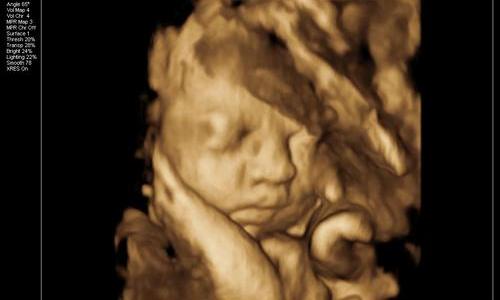

四维彩超技术的发展让准父母们得以在宝宝出生前一窥其模样,但这种先进的医学影像技术真的能准确预测婴儿出生后的相貌吗?事实上,四维彩超图像与实际出生婴儿之间存在一定的差异。

首先,我们需要了解四维彩超技术的局限性。四维彩超是通过超声波反射原理生成胎儿的三维图像,其清晰度和准确性受到多种因素的影响。正如天津河西坤如玛丽妇产医院所指出的,“虽然四维彩超的图像非常清晰,但解读图像需要专业的医学知识和经验。”这意味着,普通人在观察四维彩超图像时,可能会对胎儿的某些特征产生误解。

其次,胎儿在出生前后的变化也是导致差异的重要原因。伦琴影领诊断中心提醒:“由于四维彩超一般是在孕24-28周左右进行检查,这时候离宝宝出生还有十几周的时间。这十几周的时间里,宝宝会继续发育,这时的样貌跟出生时相比还是会发生一些变化。”随着胎儿的继续发育,其面部特征会逐渐完善,出生后的婴儿相貌自然会与四维彩超图像有所不同。

1. 面部特征:四维彩超图像中的胎儿面部可能显得较为模糊或不成比例,这是因为胎儿的面部肌肉和骨骼仍在发育中。出生后,随着婴儿的生长,其面部特征会逐渐变得清晰和协调。